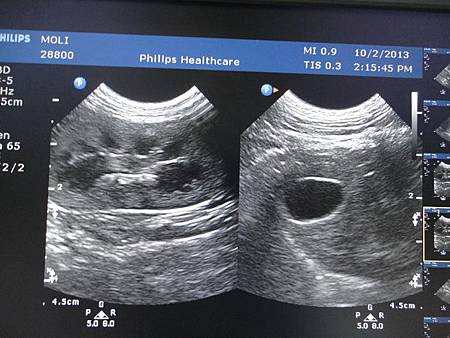

令人最煩惱的是左腎...

醫生很擔心的說,它已經萎縮了...

照片中可以看出來他的大小比右邊的小,雖說6月份才做過血檢

還有掃了膀胱,膀胱是正常的,沒有結石與結晶